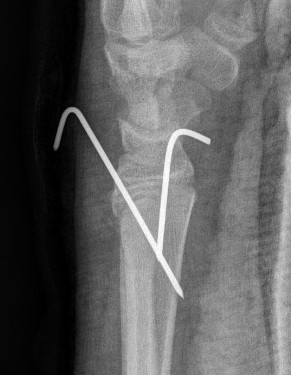

Percutaneous pinning with K wires

Indications

Unstable fractures - both bone fractures

Inadequate reduction

Loss of reduction

Ipsilateral supracondylar fractures / floating elbow

Open fractures

Technique

Radial styloid K wire

- small incision, dissect down to protect sensory radial nerve

- avoid physis if able in metaphyseal fracture

- can cross physis

Dorsal Kapaji technique K wire